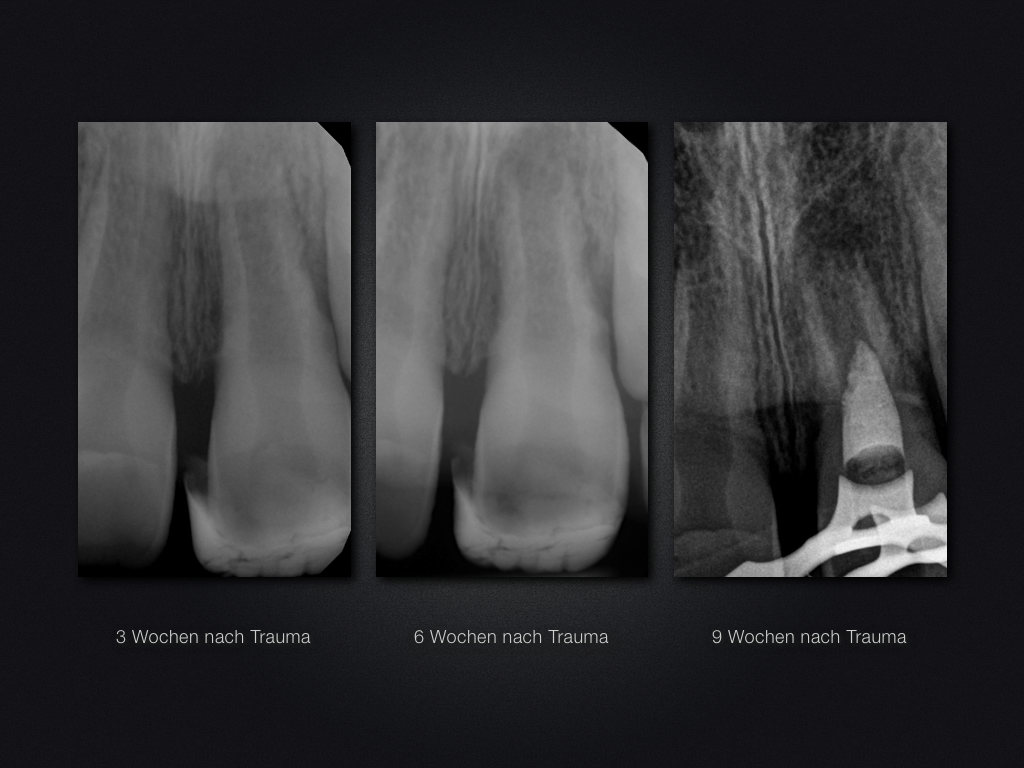

Praxistauglicher Kompromiss